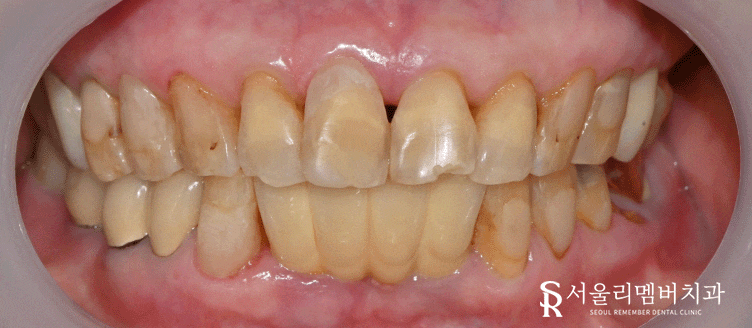

일단 여러 곳에 보철이 올려져 있었으며

군데군데 쌓여 있는 치석과, 부식된 치아들이 눈에 띄었습니다.

특히 앞니 절단 부분은 파절이 일어나 있었으며

이와 더불어 '치경부 마모증'도 관찰되고 있네요.